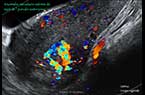

Vascularisation du corps jaune analysée par Doppler-Energie en 3D Vascularisation du corps jaune analysée par Doppler-Energie en 3D Vascularisation du corps jaune analysée par Doppler-Energie en 3D

Vascularisation du corps jaune analysée par Doppler mode Dynamic Flow, en 3D Vascularisation du corps jaune analysée par Doppler mode Dynamic Flow, en 3D Vascularisation du corps jaune analysée par Doppler mode Dynamic Flow, en 3D